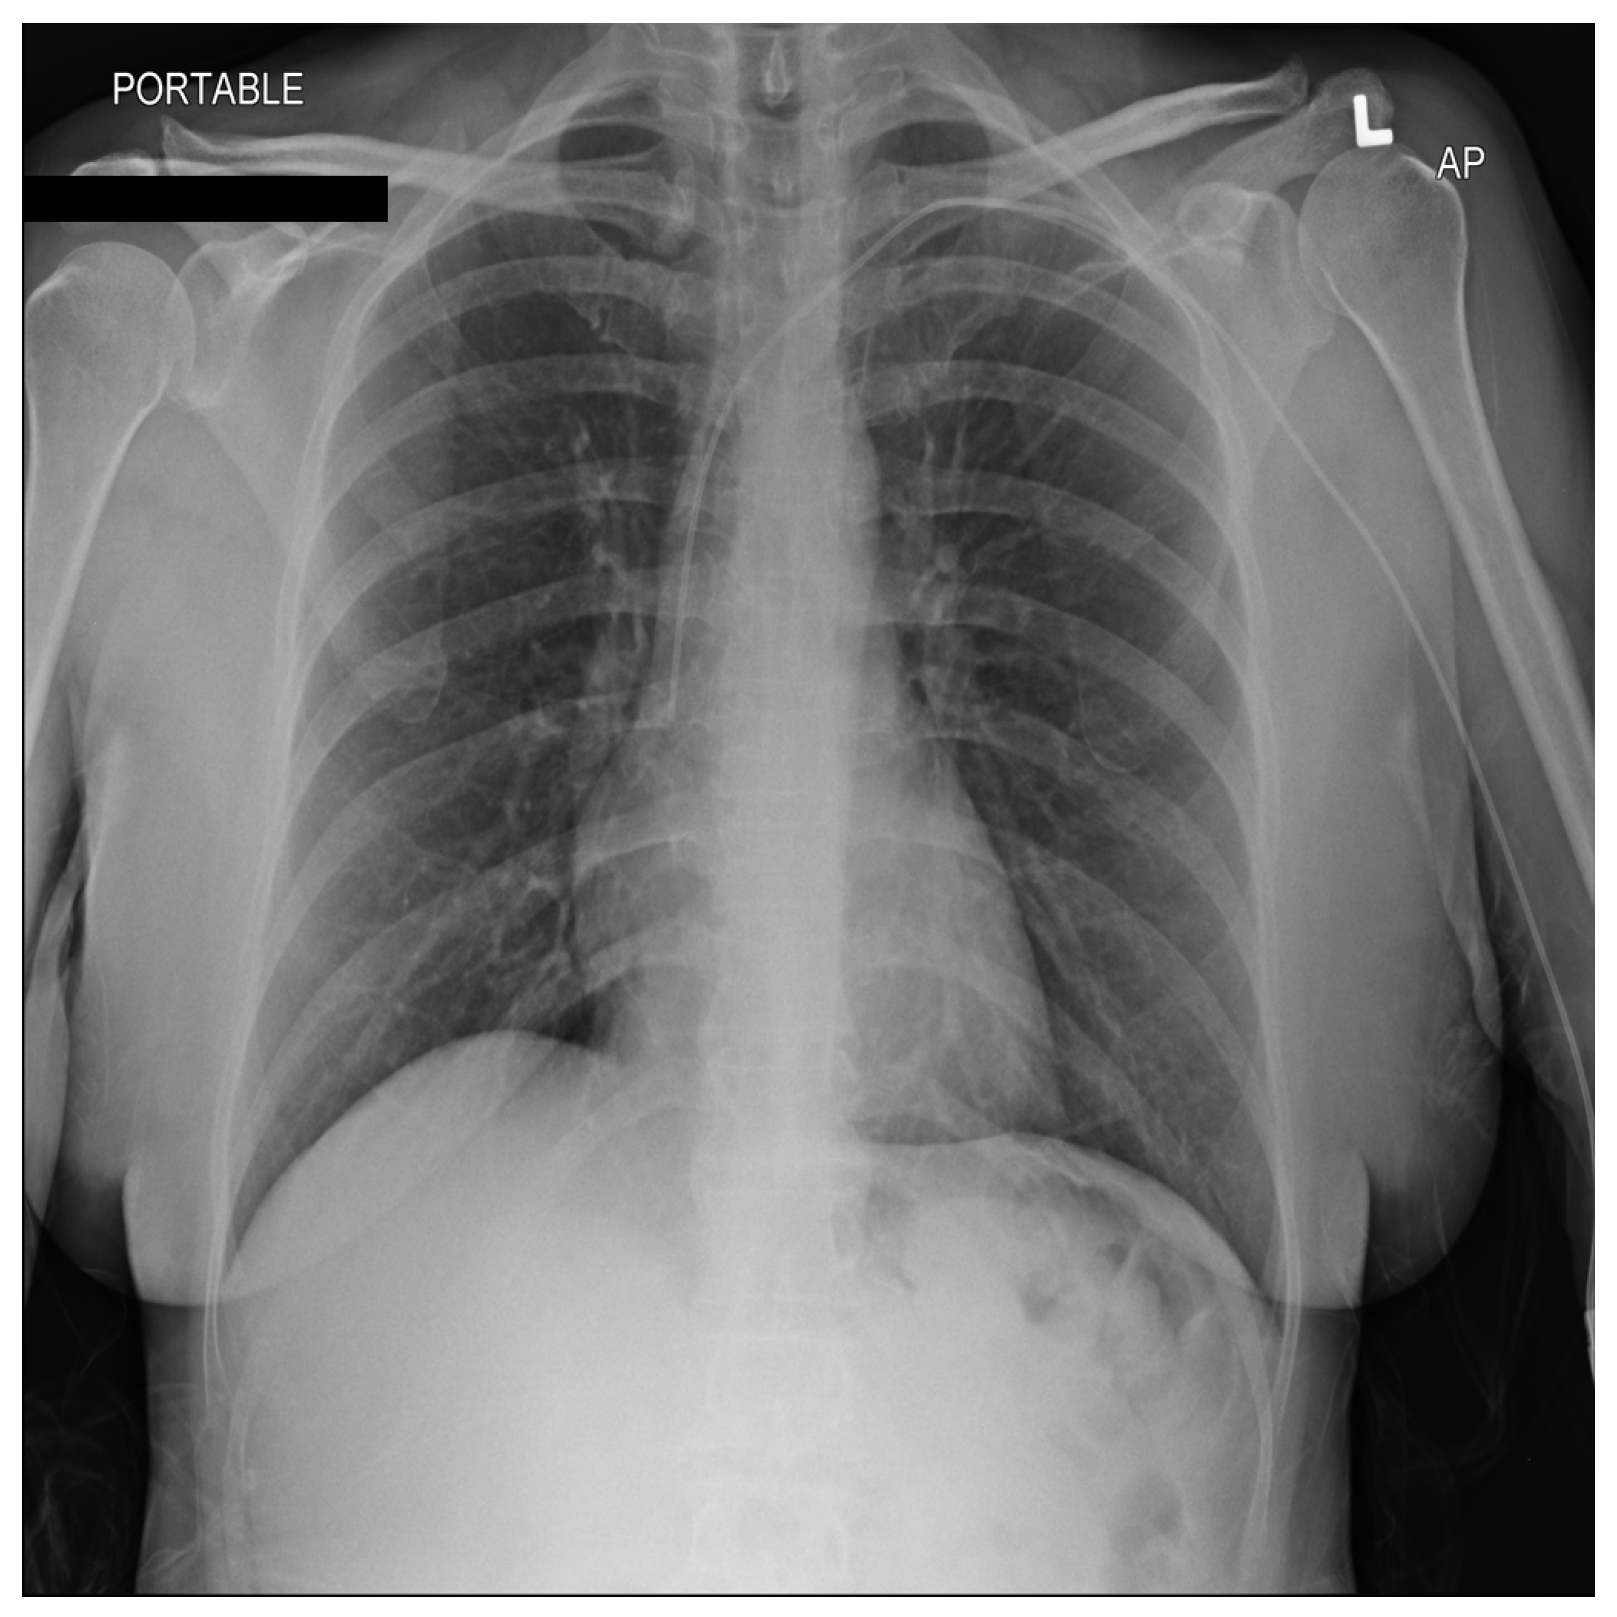

From a visual perspective, as illustrated in the comparison images above, both the RSCM as in Figure 1 and NIH as in Figure 2 datasets exhibit comparable quality in terms of resolution, clarity, and diagnostic relevance. This similarity ensures that image quality does not introduce any significant bias or variation.

Figure 1.

Sample image from the RSCM dataset. R: Right.

Figure 2.

Sample image from the NIH dataset. L: Left.